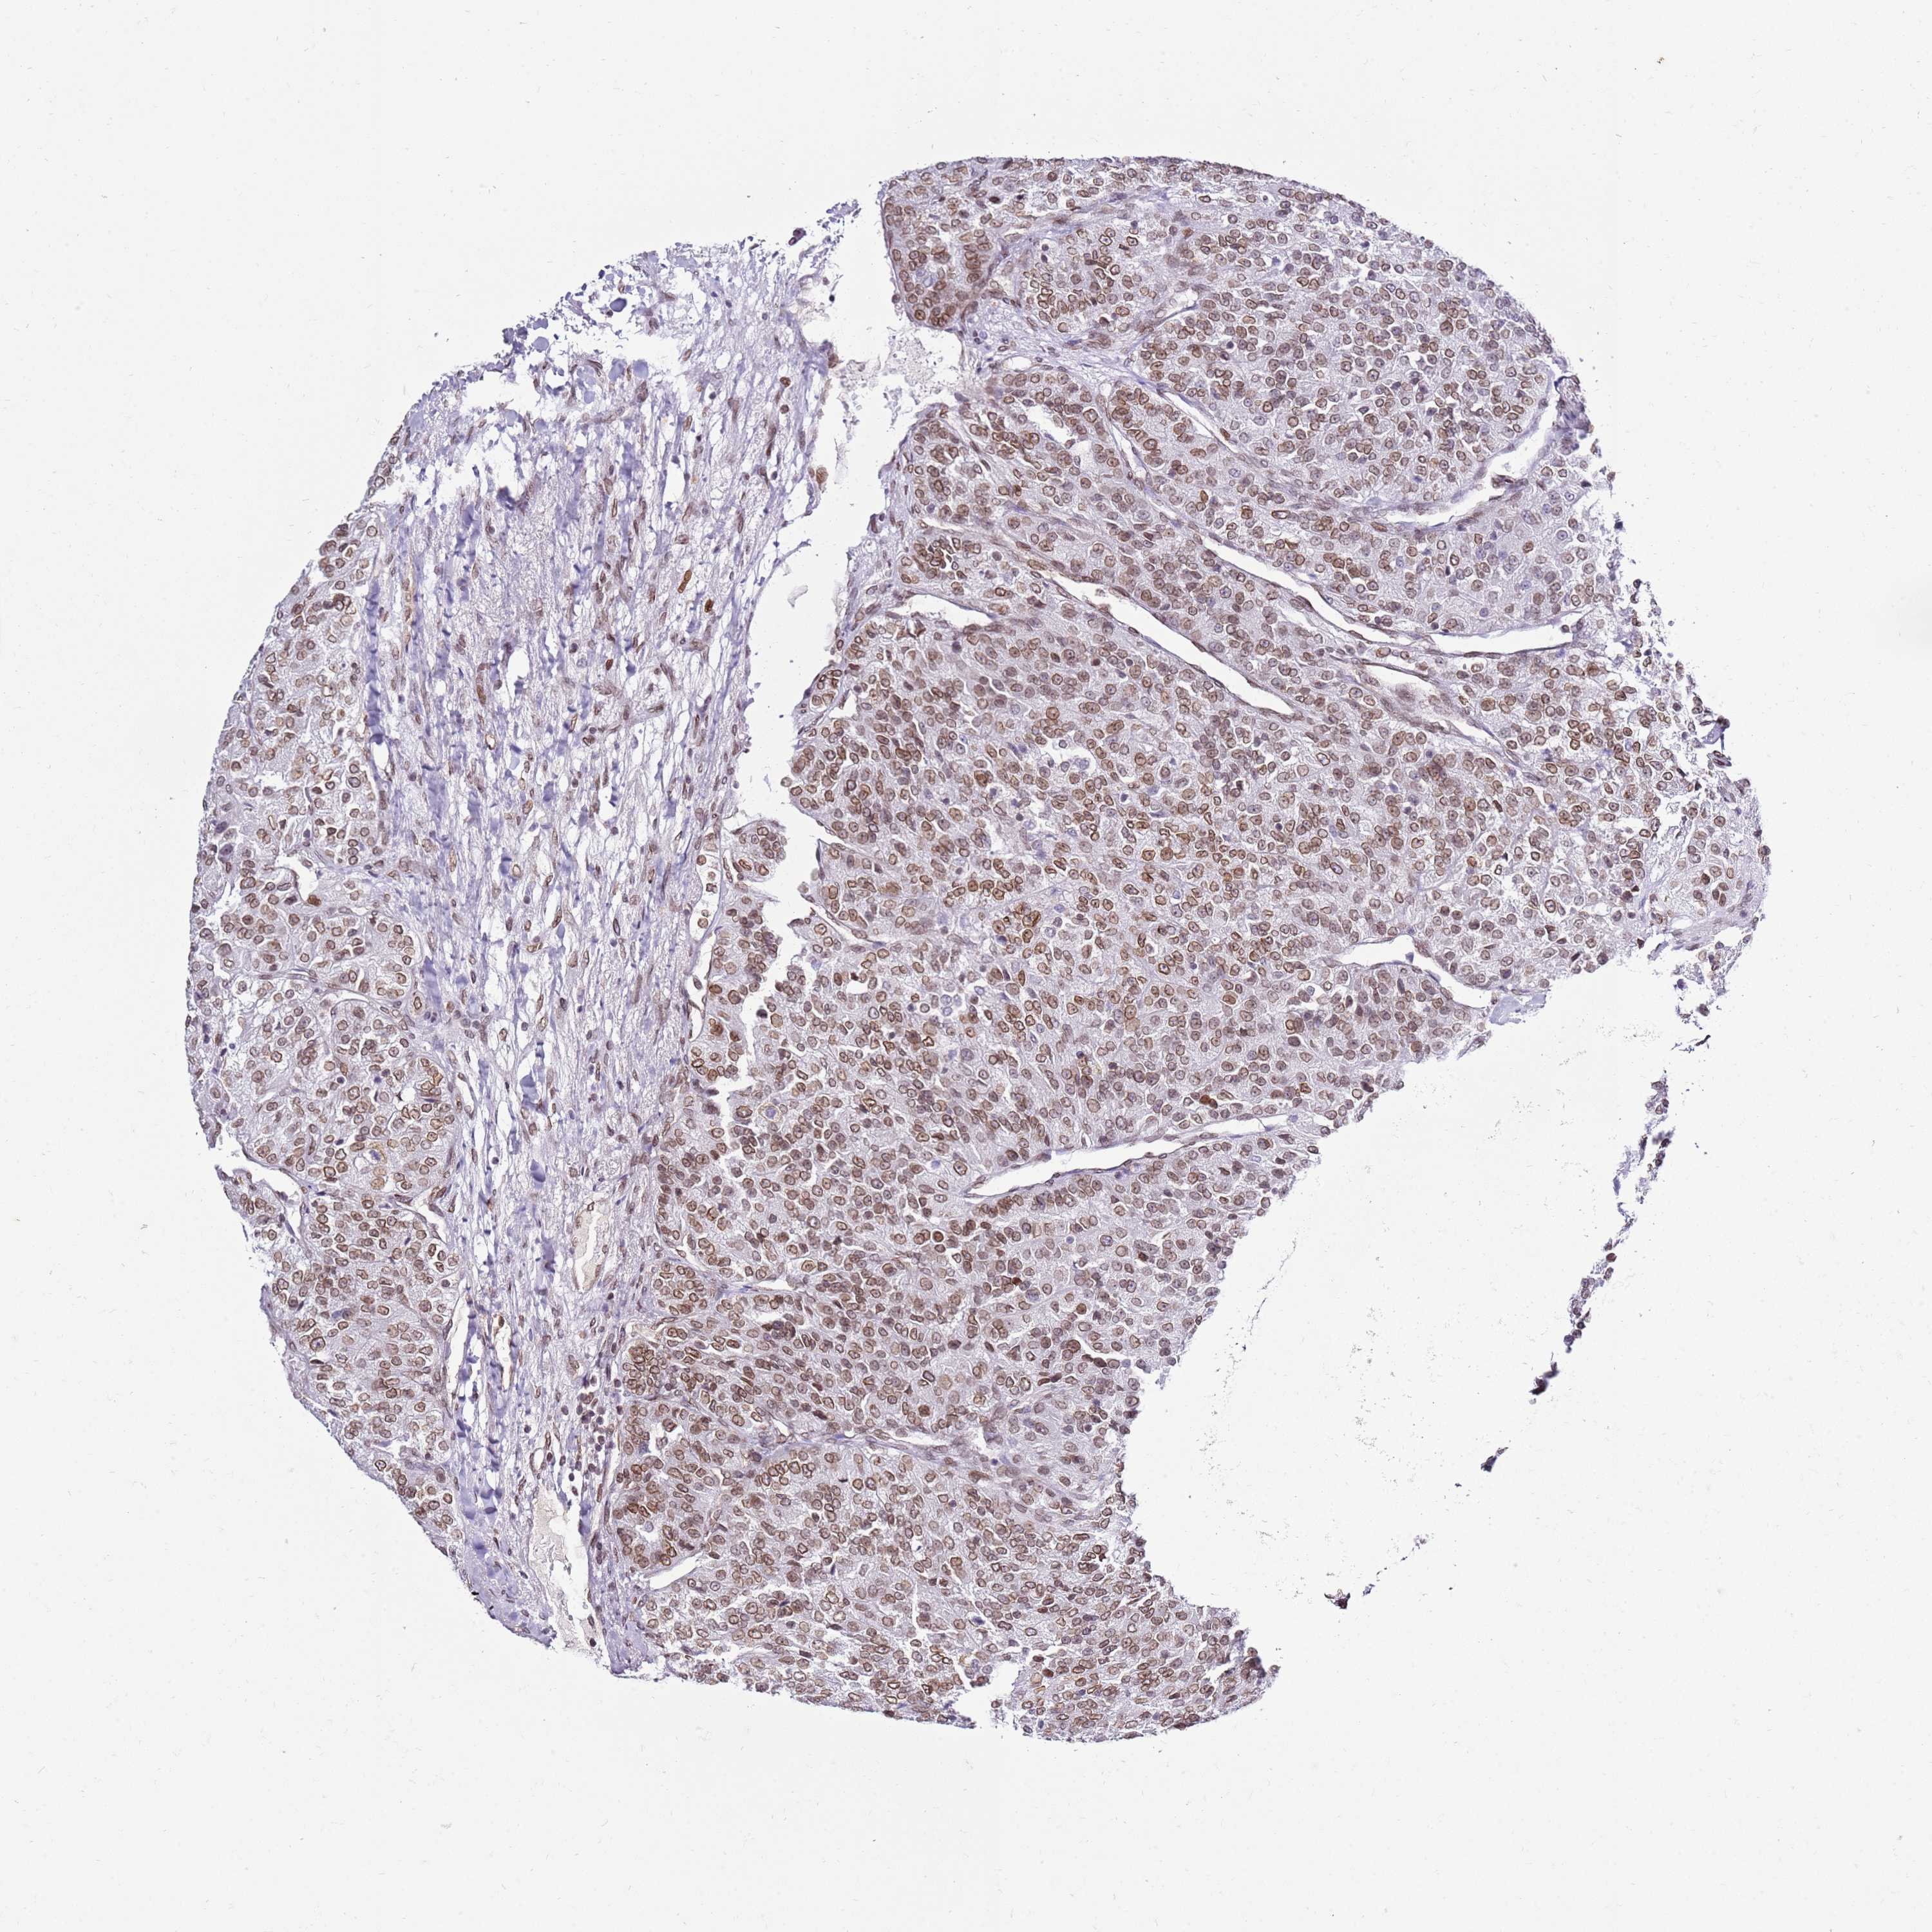

CANCER RENAL CANCER Show tissue menu

KICH TCGA KIRC TCGA KIRC VALIDATION KIRP TCGA PROTEIN RCC CPTAC PROTEIN EXPRESSION